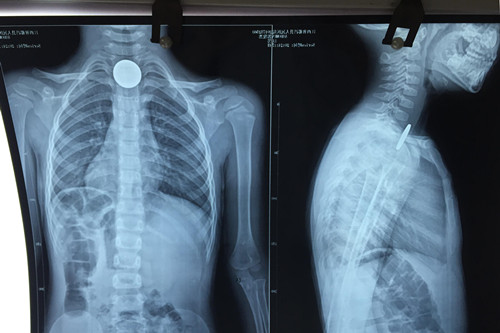

近日,一3岁患儿因误吐硬币被送临床医学院/附属医院就医,该院耳鼻喉头颈外科医生巧借导尿管成功为其取出异物,使患儿转危为安。

3岁患儿郭某,傍晚时分在家玩耍时口含一枚五角面值的硬币,不慎吞入后反复恶心、呕吐,连喝水都会引发呕吐。就近送至都昌县人民医院行胸片检查,证实硬币嵌顿于食道入口处,建议转上级医院就诊。晚上22:00左右赶到九江市,在专科医院挂急诊就诊,因无对口科室急诊,在其总值班医师的指引下,来到临床医学院/附属医院耳鼻喉科就治。当班医生游锦接诊后,成功取出硬币,稍作观察,患儿于23:30左右离院回家。

对于如何取出硬币,游医生介绍说,小儿食管异物取出比较棘手,例如这位3岁患儿,来院就治时已距误吐硬币达6小时左右,异物刺激强烈,难受哭闹,很难配合治疗。以往这种情况多采用全麻下硬质食管镜取食管异物,患者甚至需住院两至三天。从今年5月以来,临床医学院/附属医院开始利用导尿管来取小儿食管异物这一新方法,现已成功治疗了数十名误吞异物的小朋友。因为导尿管柔软细小,引起咽反射轻微,不会引起患儿的较大恐惧感, 在表麻或者局麻下即能配合,手术安全高效。大部分情况下也不需住院,花费明显减少。